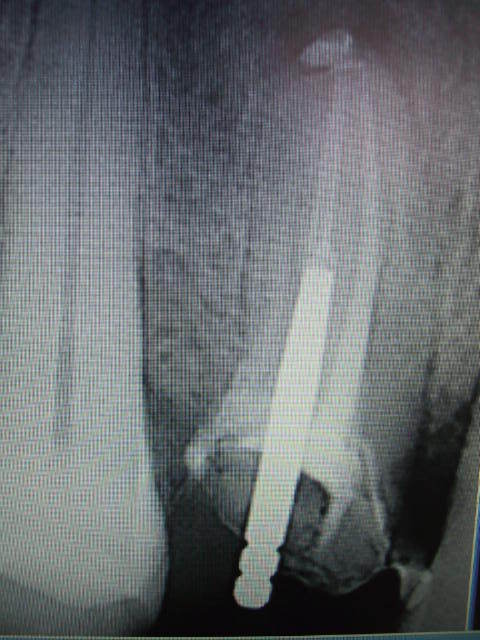

allez on ressaye -------------------------------------adhoc t'es un frère pour moi-------------------et t'as vu y a de la couleur----------------------avant tout promettez moi de ne pas en parler à Raoul,il pourrait avoir une mauvaise image de la dentisterie française et cela pourrait faire tourner le lait des kangourouses-------------------revenons au sujet, que faire?? :ED OU HN? Attendre le mois de mai?appeler la cnsd ou l'ujcd? y a plus personne.Peut etre mon comptable? prendre un avocat?appeler le dentiste conseil?Je me faire remarquer? je risque un controle?que dire au patient?adhoc m'a dit tte vérité n'est pas bonne à dire. Je risque de passer pour un collabo?Ou faire une dépression?Je me sens pas bien,aidez moi je vous en supplie, j'en peu plus...Et clochette qui m'attend..........

Allez, peterpan, un beau geste; un traitement correct avec un tenon qui n'est pas sur 3 mm,mais sur 6 ou plus; allez cherche bien dans ton musée, tu vas trouver, YESSSS.

Peterpan,la deuxième photo c'est quoi comme gateau

c'est un peu flou,clafoutis?

non non annie, c'était de la vraie hum hum sous la couronne vas voir la 2eme photo, une fois nettoyée ça fait moins claffoutis ,attend la suite ,j'ai mieux pour plus tard, bonne nuit